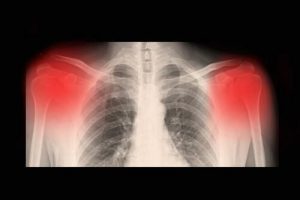

Diagnosen stilles af din læge. Normalt tager din læge et røntgenbillede eller bruger en CT og / eller en MR scanner. Ultralyd med høj opløsning kan desuden måle, hvor fremskredent din sygdom er.